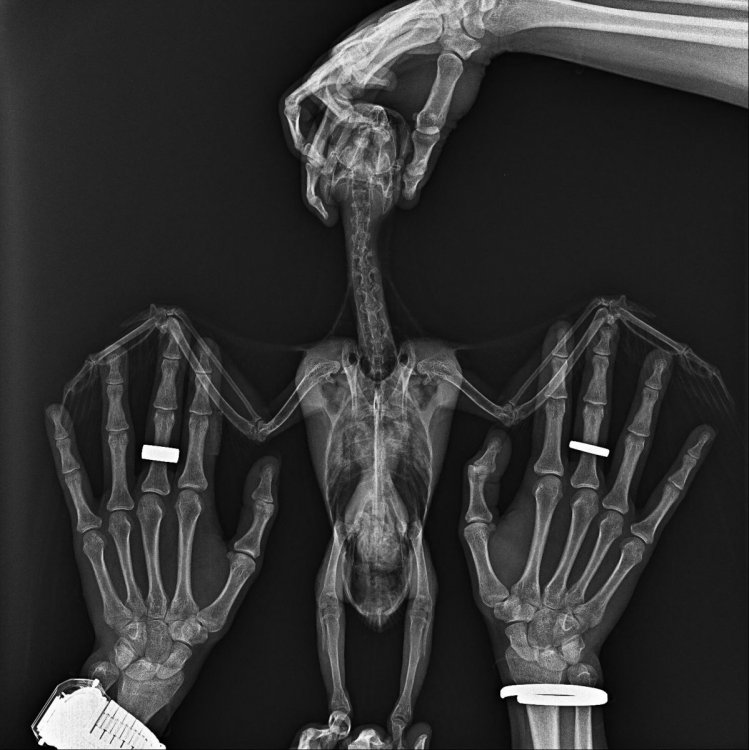

Arkasha18 Опубликовано 6 апреля, 2023 Автор #5 Опубликовано 6 апреля, 2023 в общем по итогу стул , то нормальный, то нет, прием доктора я тогда отменил, но тут он сильно заболеле и пришлось все таки отвезти, сделали рентген , взяли все анализы, не чего супер серьезного не нашли, но есть какие то на рентгене не пятна, сказали что это может быть ошибка ...нашли каието в помете грибы ...или что то там такое...в общем прописали всякого + антибиотик...и смотреть динамику надо сказали.

Arkasha18 Опубликовано 20 апреля, 2023 Автор #6 Опубликовано 20 апреля, 2023 Птица умерла ( только смог отойти от истории этой что бы что то написать. Куплена была птица у Андрея Михайлова возрастом 3 мес, на вторую неделю вот тут я писал что стул не нравится. но признаков болезни не была. птица была активная. Заводчик отговорил нести к доктору мотивировав что там его заколят, будет только хуже. через неделю птица простыла. я купил лампу ИК и черз два дня все прошло. Примерно через месяц после покупки попугая он опять заболел. пытались под лампой держать в отдельной комнате с теплыми полами. на третий день было понятно что что то серьезное. Он перестал кушать. сидел в низу клетки. понесли к доктору. были сделаны анализы. снимки. выписаны антибиотики. вечером мы его по поили антибиотиками. утром он был очень слаб уже. решили немного его покормить кашей 7 злаков без добавок со шприца. 5 кубов где то скормил. в 12 дня птица умерла. Вес был нормальный 500г. когда заболел скинул до 450 не уследил за какой период. Во всей этой истории очень грустно отношение ветеринаров. не хочу вдаваться в подробности но столько гадости в наш адрес было сказано что я в шоке. что нам птицу доверять нельзя и т/п/ я если честно в шоке. Заводчик отказался от компенсаций и отрекнулся тоже от происходящего. История ужасная еще тем что у меня жена беременная сильно все это переживала. я очень хочу купить еще одного птенца. теперь уже с анализами всеми и карантином как положено. но очень боюсь что повториться ситуация. это просто будет невыносимо. мы очень сильно горевали и до сих пор слезы наворачиваются. на видео последние минуты жизни ( вскрытие мы отказались делать потому что это и так было все сложно очень для нас. Посоветуйте как покупать новую птицу? где покупать. как обезопасить себя от таких ситуаций. рентген